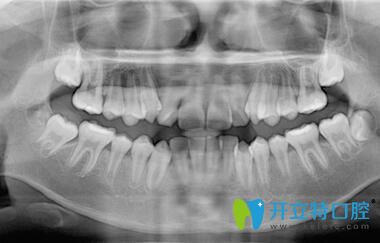

深圳正夫口腔的正畸醫(yī)生面診后,說我的牙齒屬于牙列不齊、前牙擁擠;針對我的情況,又拍了牙片;然后才制定矯正方案,建議戴傳統(tǒng)金屬托槽或球面自鎖托槽,也把這兩種牙套的優(yōu)缺點和價格都做了詳細的介紹。

我在深圳正夫口腔做牙齒矯正前拍片